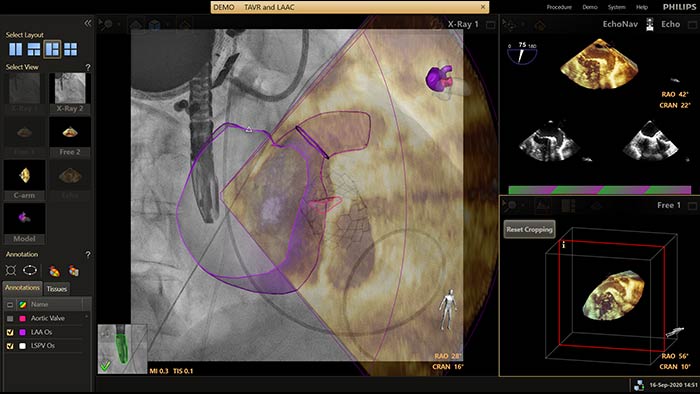

EchoNavigator verknüpft Ultraschall- und Röntgendaten auf eine völlig neue Weise in einer erweiterten Darstellung als Führungshilfe und zur Beurteilung der Orientierung von Instrumenten und Gewebestrukturen. Beim Verschließen des linken Vorhofohrs bietet EchoNavigator folgende Möglichkeiten für höhere Sicherheit und Effizienz: